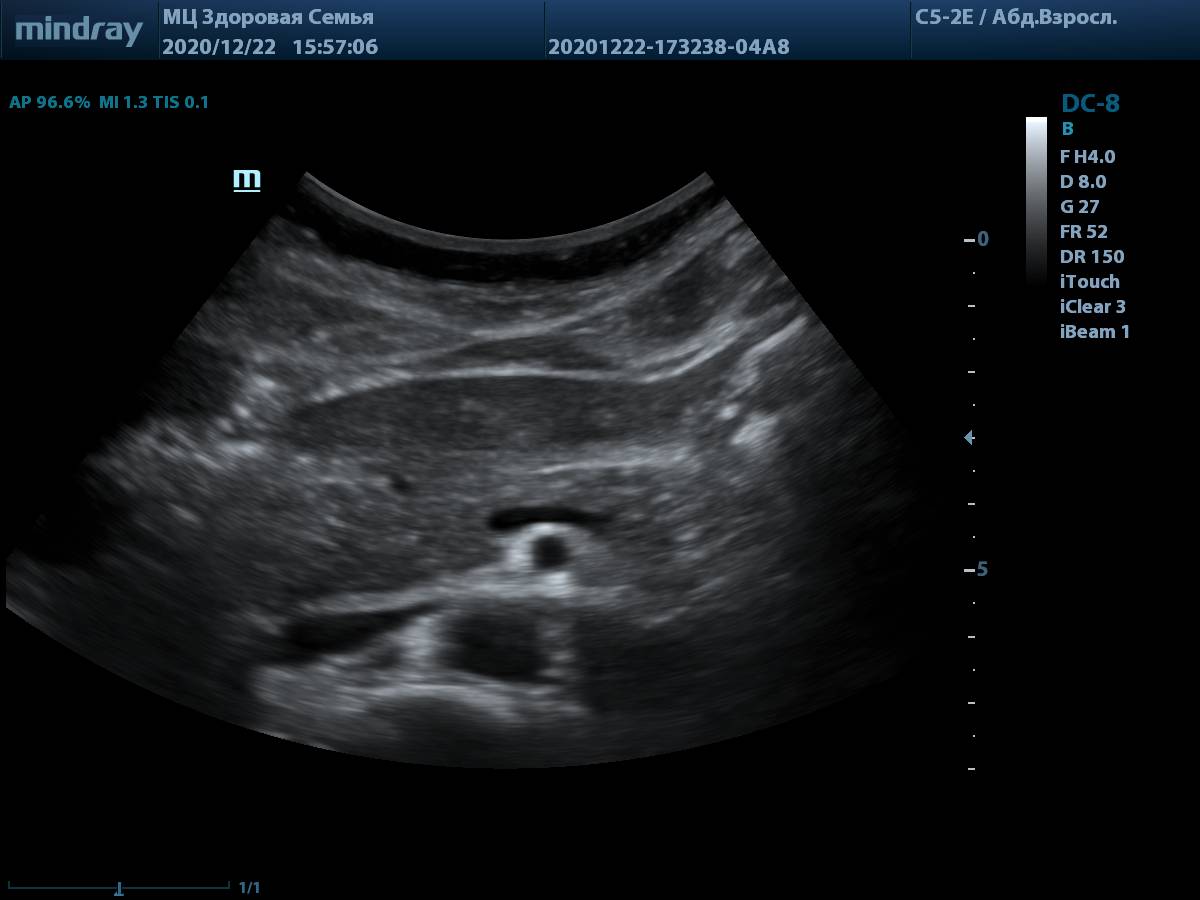

Сегодня мы предлагаем посмотреть на настоящие снимки и видео петли, полученные на живом потоке пациентов. Такие изображения встречаются в клинической практике ежедневно у пациентов без идеального ЭХО окна. Снимки выполнены на аппарате экспертного класса Mindray DC-8.

4. Пример визуализации поджелудочной железы у пациента с избытком массы тела, проблем с измерением органа и оценки его структуры нет. В качестве линзы использована левая доля печени.